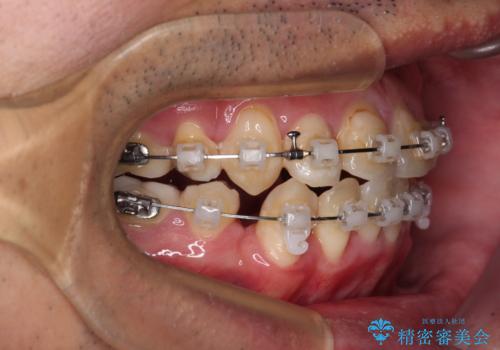

- 矯正装置

- クリアブラケット

上下ともに八重歯が顕著であったので、上下左右第一小臼歯4本を抜歯し、ワイヤー装置にて矯正治療を行うこととしました。

デコボコが強いことが原因で歯間部に汚れが溜まりやすい状態でしたが、矯正前にできる限り汚れが少なくなるようにブラッシングなどの指導を行い、口腔状態が改善された後にワイヤー装置を装着することとしました。